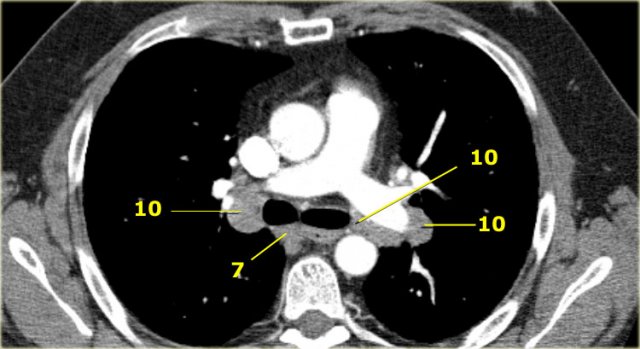

10. Hạch rốn phổi (Hilar nodes)

Bao gồm các hạch nằm cạnh phế quản gốc và các mạch máu rốn phổi).

Ở bên phải đi từ bờ dưới tĩnh mạch Azygos đến thùy trên phổi.

Ở bên trái đi từ bờ trên của động mạch phổi đến thùy trên phổi.

10. Rốn phổi

10. Hạch rốn phổi

Hạch gần thùy phổi, xa màng phổi trung thất và nằm gần phế quản trung gian bên phải.

Hạch 10-14 thuộc nhóm N1 vì không nằm trong trung thất.

7. Hạch dưới carina (Subcarinal)

7. Dưới carina

7. Hạch dưới carina

Nằm ở phía dưới góc carina của khí quản, nhưng không liên quan với thùy dưới hoặc thùy trên của phổi.

Ở bên phải chúng kéo dài đến bờ dưới của phế quản trung gian.

Ở bên trái chúng kéo dài đến bờ trên của phế quản thùy dưới.